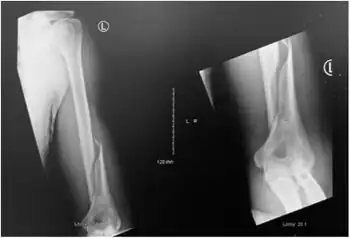

| Holstein–Lewis fracture at 5 weeks post fracture | |

A Holstein–Lewis fracture is a fracture of the distal third of the humerus resulting in entrapment of the radial nerve.